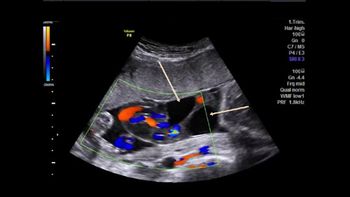

QUIZ: What's causing the compression of the fetal heart (tubular shaped), ascites and dilated trachea?